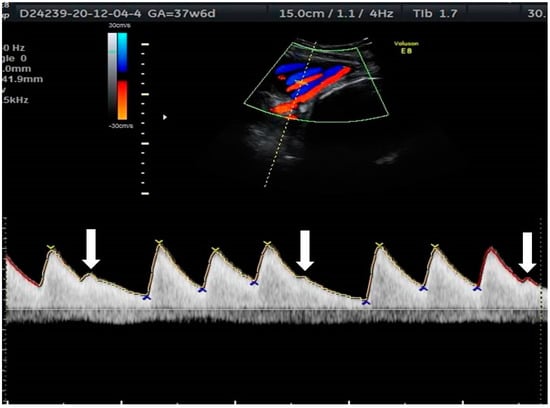

2. The Use of Ultrasound to Assess Fetal Heart Rhythm

5.3. Blocked Ectopic Beats